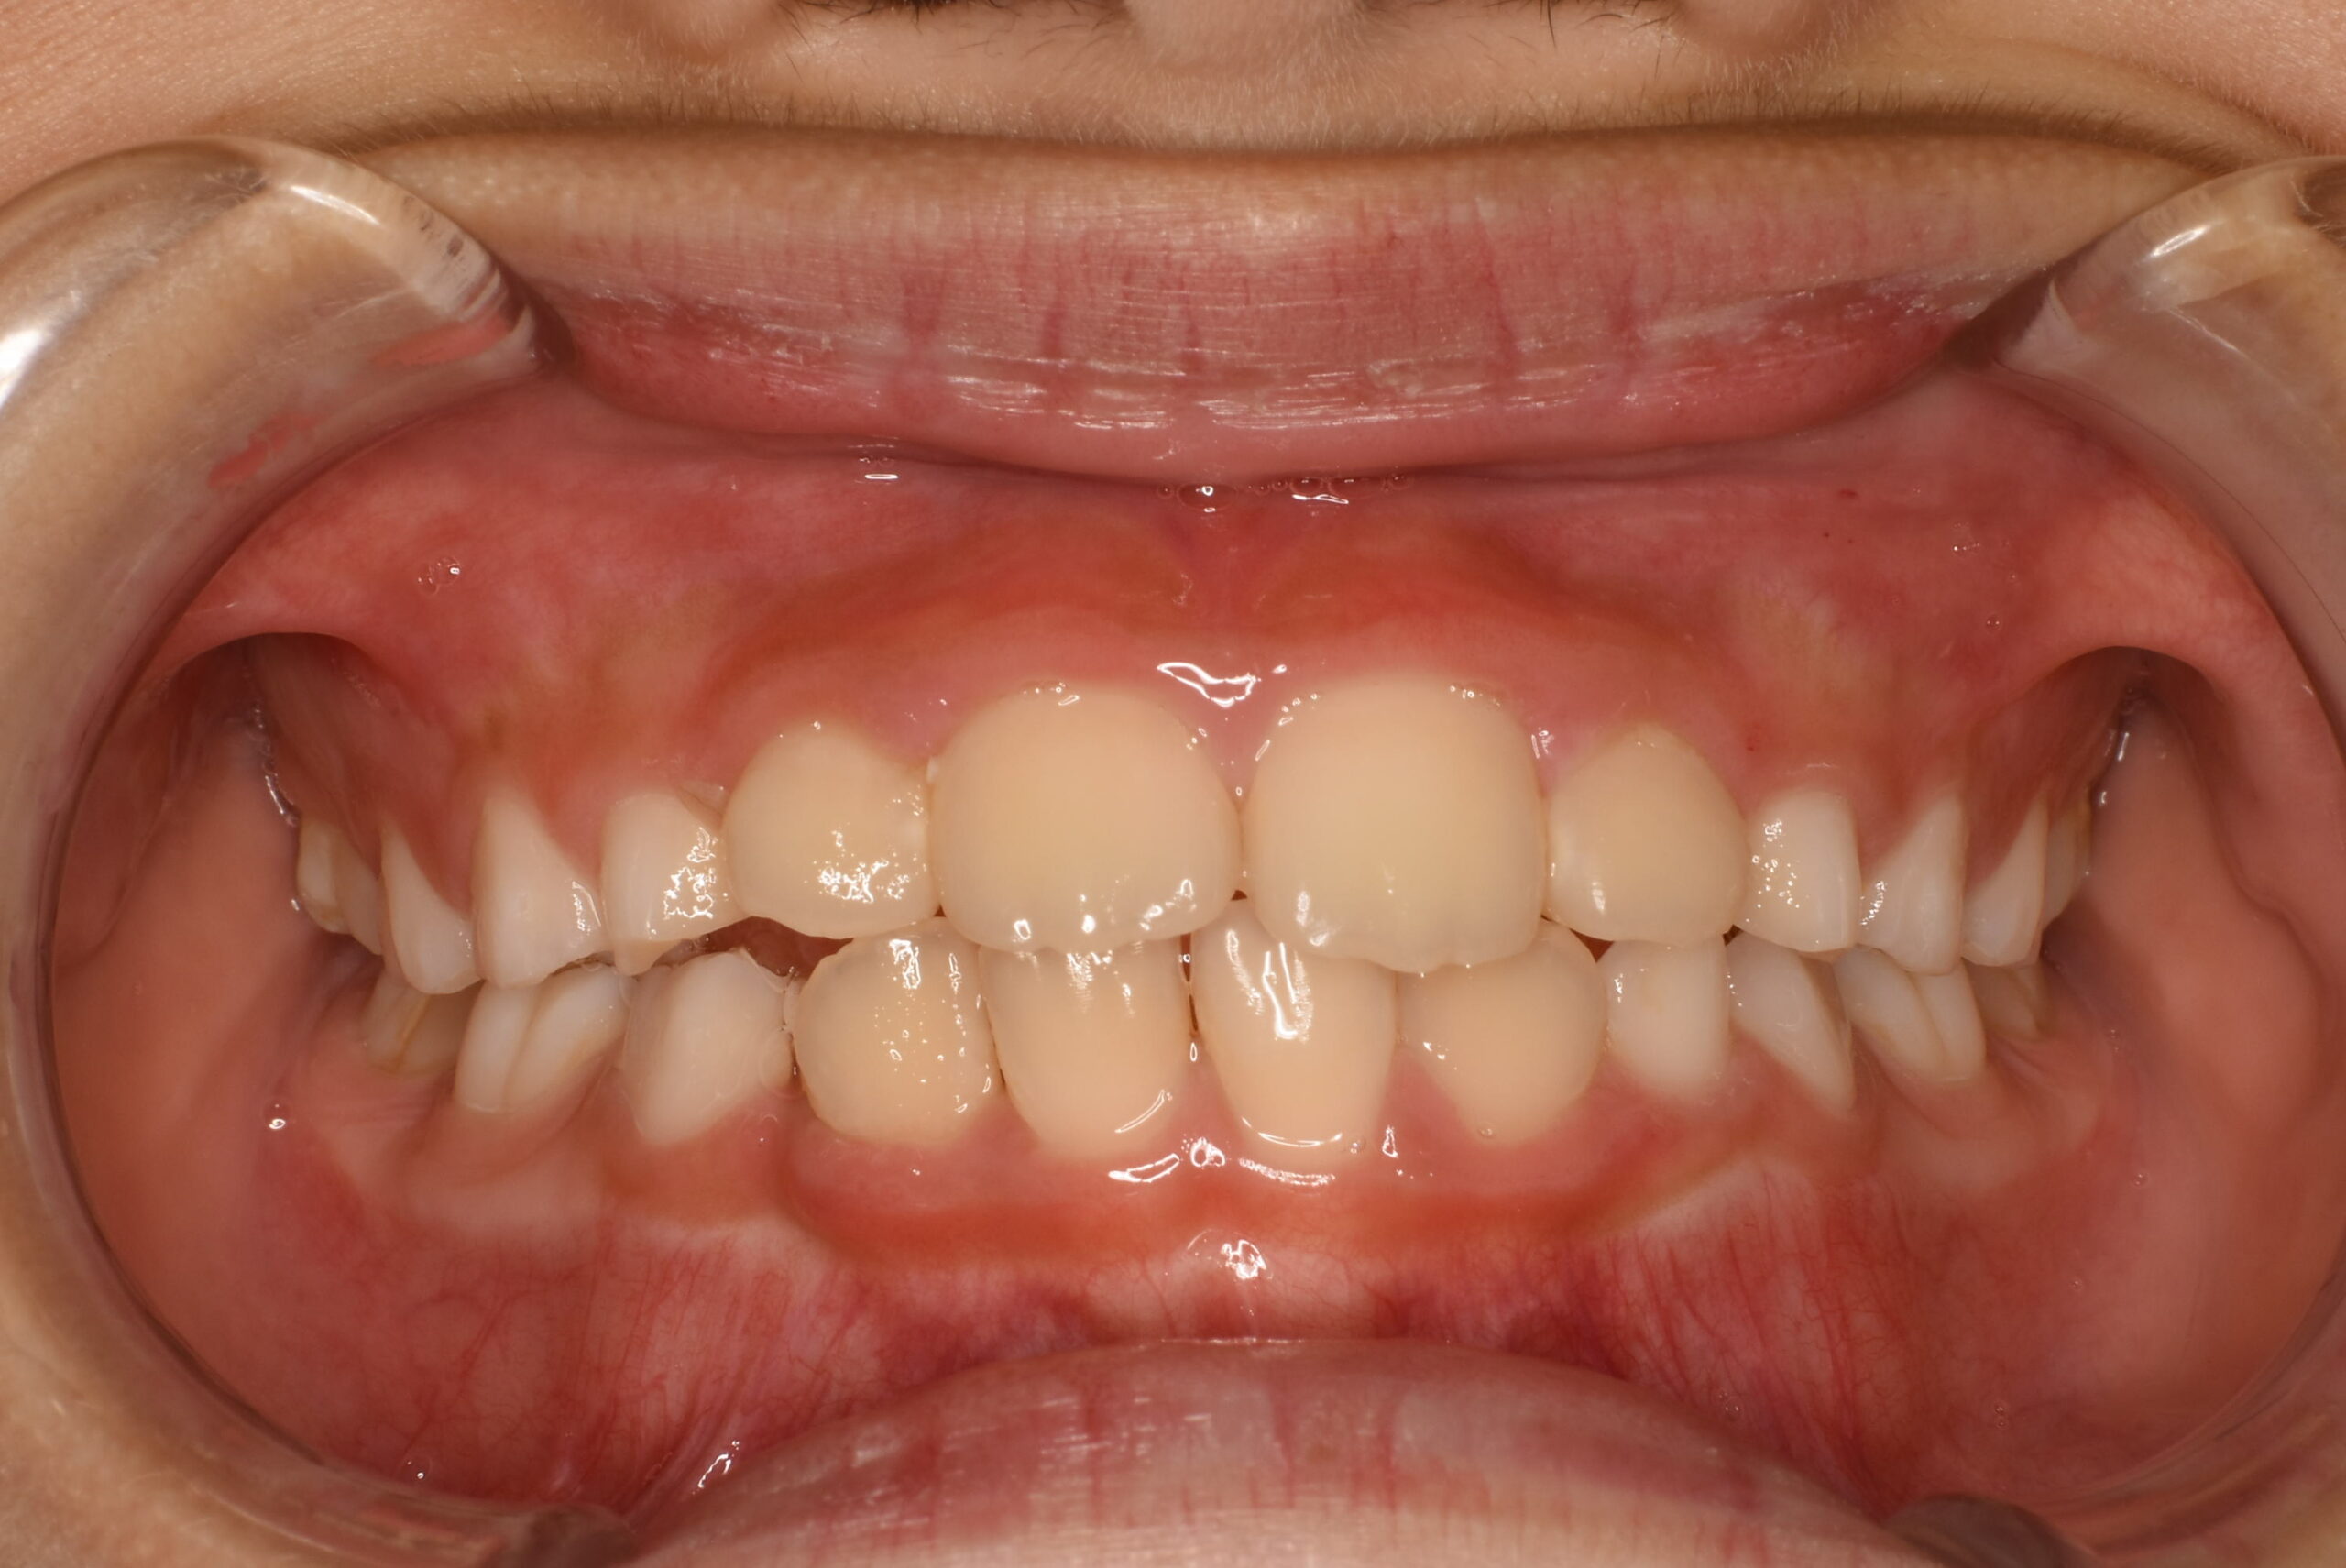

| 主訴 | 出っ歯 |

|---|---|

| 年齢・性別 | 女児・10歳(小学4年生) |

| 診断名 | 上顎前突(出っ歯)、口呼吸および舌の癖 |

| 治療内容 | 日中1時間と就寝時のマウスピース装着に加え、呼吸・舌・飲み込み・唇を鍛えるトレーニング(アクティビティ)を毎日実施。 |

| 治療期間 | 2年2か月(現在も継続中) |

| 費用(税込) | 583,000円 ※検査代・装置代・月1回調整料5,500円含む |

| リスク・副作用 |

|

| 備考 | 本症例は治療途中の経過写真です。治療結果には個人差があります。 |